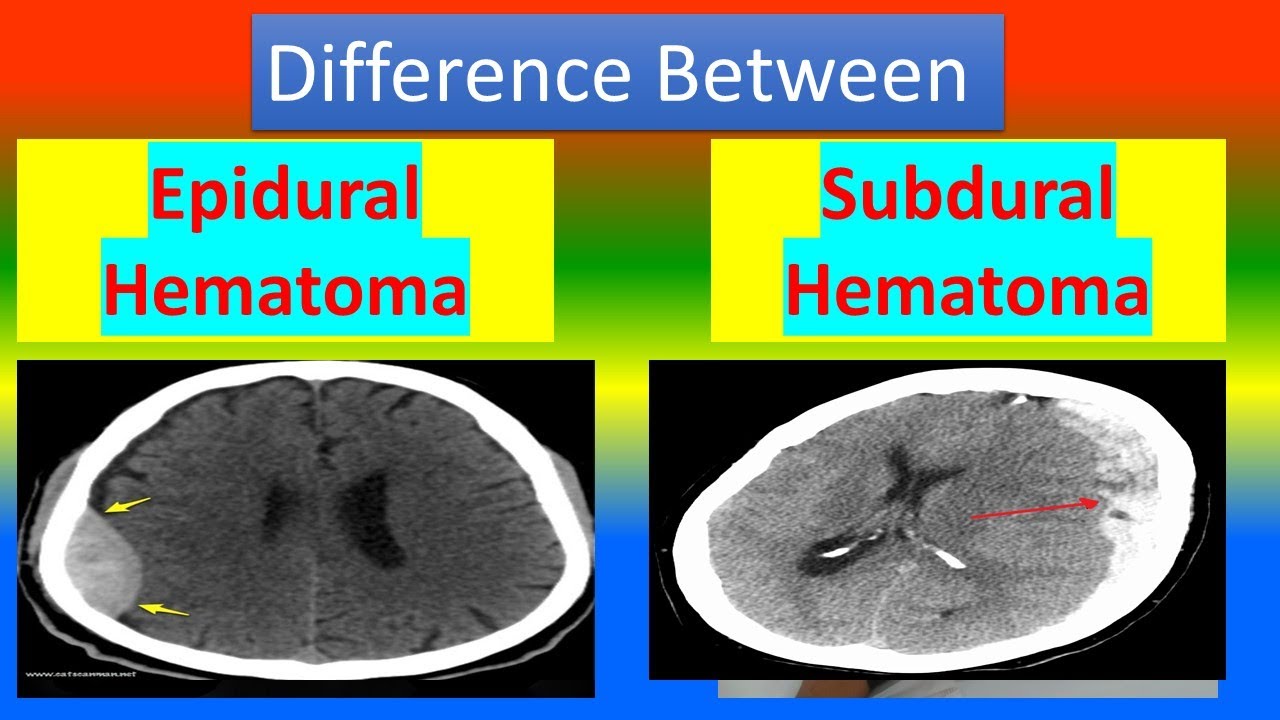

Epidural Hematoma Vs Subdural Hematoma Understanding The Differences It’s important to know the difference between a stroke and a subdural hematoma. both are serious brain issues that can cause big problems. strokes and subdural hematomas are sudden events that affect the brain a lot. what is a stroke? a stroke happens when a blood vessel in the brain gets blocked or bursts. Stroke and subdural hematoma are interconnected and can have devastating effects. understand the link between these two serious medical conditions and how they impact brain health. It’s hard to tell the difference between a subdural hematoma and a stroke. both are serious, but they come from different causes and need different treatments. a subdural hematoma is when blood gathers between the brain and its outer layer. a stroke, or cerebrovascular accident, happens when blood doesn’t reach part of the brain. The only way to differentiate between stroke and chronic subdural hematoma, regardless of symptoms, is with a ct scan of the brain. don’t assume that someone’s symptoms must mean chronic subdural hematoma just because he hit his head recently, either; it can still be a stroke, unrelated to the head trauma.

Download Subdural Hematoma Vs Epidural Hematoma Intracranial It’s hard to tell the difference between a subdural hematoma and a stroke. both are serious, but they come from different causes and need different treatments. a subdural hematoma is when blood gathers between the brain and its outer layer. a stroke, or cerebrovascular accident, happens when blood doesn’t reach part of the brain. The only way to differentiate between stroke and chronic subdural hematoma, regardless of symptoms, is with a ct scan of the brain. don’t assume that someone’s symptoms must mean chronic subdural hematoma just because he hit his head recently, either; it can still be a stroke, unrelated to the head trauma. Subdural hematoma: bleeding between the brain and the dura mater, the outermost membrane covering the brain. now, you might be wondering, “are all brain bleeds considered strokes?” the answer is no. while hemorrhagic strokes are a type of brain bleed, not all brain bleeds meet the criteria for a stroke. A subdural hematoma, on the other hand, is a collection of blood between the brain and its outermost covering (the dura mater), often caused by head trauma. both can lead to neurological. There are several types, each with its own set of challenges: 1. intracerebral hemorrhage: bleeding directly into the brain tissue. 2. subarachnoid hemorrhage: bleeding in the space between the brain and the thin tissues that cover it. 3. subdural hematoma: bleeding between the brain and the dura mater, the brain’s tough outer covering. 4. A subdural haematoma is a serious condition where blood collects between the skull and the surface of the brain, causing pressure on the brain and damaging it. it is a form of bleeding inside the head, specifically in the subdural space, which is the area between the dura mater and the arachnoid mater—two of the three layers of tissue.

Hematoma Epidural Vs Hematoma Subdural Vrogue Co Subdural hematoma: bleeding between the brain and the dura mater, the outermost membrane covering the brain. now, you might be wondering, “are all brain bleeds considered strokes?” the answer is no. while hemorrhagic strokes are a type of brain bleed, not all brain bleeds meet the criteria for a stroke. A subdural hematoma, on the other hand, is a collection of blood between the brain and its outermost covering (the dura mater), often caused by head trauma. both can lead to neurological. There are several types, each with its own set of challenges: 1. intracerebral hemorrhage: bleeding directly into the brain tissue. 2. subarachnoid hemorrhage: bleeding in the space between the brain and the thin tissues that cover it. 3. subdural hematoma: bleeding between the brain and the dura mater, the brain’s tough outer covering. 4. A subdural haematoma is a serious condition where blood collects between the skull and the surface of the brain, causing pressure on the brain and damaging it. it is a form of bleeding inside the head, specifically in the subdural space, which is the area between the dura mater and the arachnoid mater—two of the three layers of tissue.

Differences Between Subdural And Epidural Hematoma Epidural Hematoma There are several types, each with its own set of challenges: 1. intracerebral hemorrhage: bleeding directly into the brain tissue. 2. subarachnoid hemorrhage: bleeding in the space between the brain and the thin tissues that cover it. 3. subdural hematoma: bleeding between the brain and the dura mater, the brain’s tough outer covering. 4. A subdural haematoma is a serious condition where blood collects between the skull and the surface of the brain, causing pressure on the brain and damaging it. it is a form of bleeding inside the head, specifically in the subdural space, which is the area between the dura mater and the arachnoid mater—two of the three layers of tissue.